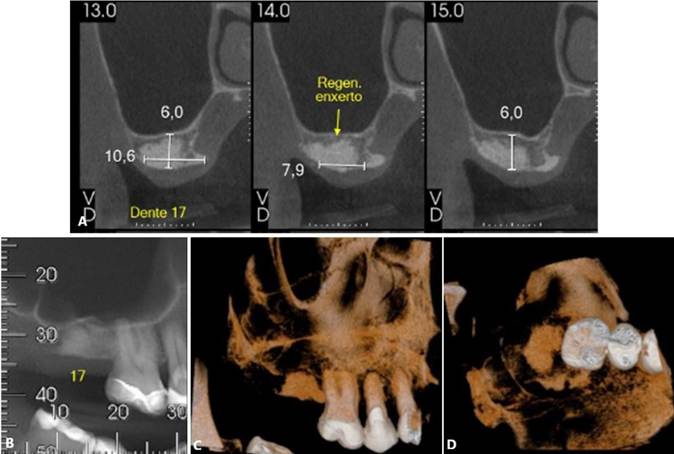

Paciente S. M. T, gênero masculino, 62 anos de idade, compareceu ao consultório particular queixando-se de sintomatologia dolorosa na região do 27. O paciente relatou presenta de insuficiência renal crônica, em tratamento através da hemodiálise. Ao exame clínico e radiográfico, foi proposto a exodontia dos elementos dentários 17 e 27, devido a perda óssea periodontal significativa, inviabilizando a sua manutenção. No mesmo tempo cirúrgico da exodontia, foi realizado a preservação alveolar com enxerto (Bio-Oss, Geistlinch, Wolhusen – Suíça) e membrana (Bio-Gide, Geistlinch, Wolhusen – Suíça). As figuras 15 (A – C) e 16 (A – C) ilustram a TCFC após a extração. Posteriormente, foram instalados implantes curtos ARCSYS (FGM, Joinvile – SC, Brasil) 3,8 mm x 7,0 mm na região do 17, e 4,3 mm x 5,0 mmARCSYS (FGM, Joinvile – SC, Brasil) no 27. O acompanhamento clínico e radiográfico realizado durante 04 anos, com resultados satisfatórios.

Figura 15. A – C) – Tomografia computadorixada de feixe curto (TCFC) evidenciado região edêntula do 17, após exodontia.

Figura 16. A – C) Figura 15. A – C) – Tomografia computadorixada de feixe curto (TCFC) evidenciado região edêntula do 27, após exodontia.